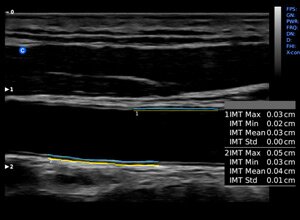

Клинические изображения